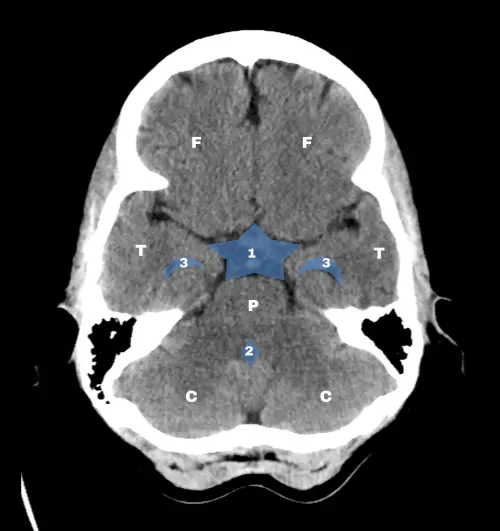

El doctor James Smirniotopoulos, neuroradiólogo y profesor universitario, propuso que bastaba con reconocer tres cortes axiales estratégicos para tener una idea global de la anatomía cerebral en la TC.

Los tres niveles clave son: el tronco encefálico, los ganglios basales y los ventrículos laterales. Una vez dominados, resulta mucho más sencillo interpretar variaciones y detectar alteraciones.

En el corte del tronco encefálico, es importante ubicar la cisterna supraselar (con su forma en estrella de  cinco puntas), el cuarto ventrículo y las prolongaciones temporales de los ventrículos laterales.

Estos elementos son puntos de referencia para evaluar tanto la anatomía normal como desplazamientos o efectos de masa.